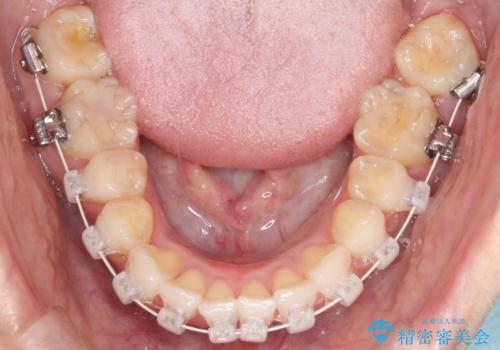

- 審美装置

- 前歯の凸凹と口元の突出感を主訴に来院されました。

臼歯関係が上顎前突傾向のため、上の小臼歯を抜歯してワイヤー矯正を行なっております。

下顎の叢生はIPRを行なって配列しています。